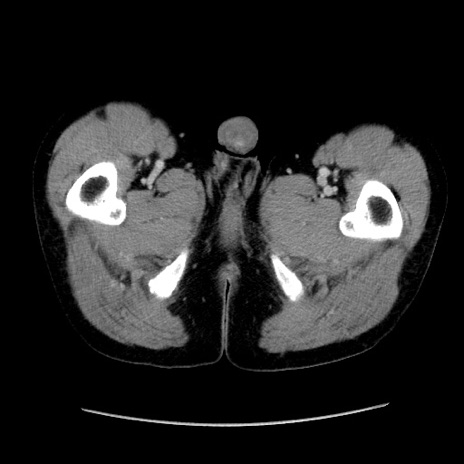

症例37(横断像)

【症例】40歳代 男性

【主訴】腹痛

【現病歴】4時間ほど前に電車に乗車中に臍部上より腹痛出現。徐々に増悪し起立困難となり、救急外来受診。生ものは数日食べていない。今朝お雑煮を食べた。

【身体所見】BT 36.8℃、BP 117/84mmHg、HR 91/min、SpO2 97%、苦悶様、腹部:臍上部広範囲圧痛あり、反跳痛±

【データ】WBC 8100、CRP 0.03